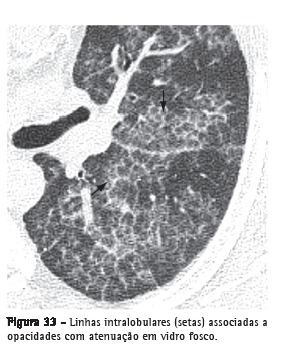

Linhas intralobulares

Caracterizadas na TCAR como imagens lineares finas no interior do lóbulo pulmonar secundário e, quando acentuadas, resultam em um aspecto rendilhado fino (Figura 33). Este achado pode ser encontrado em diversas situações, destacando-se as doenças fibrosantes (por ex.: pneumonia intersticial usual) e aquelas associadas ao padrão de pavimentação em mosaico (por ex.: proteinose alveolar).(3,54)

Ver também Padrão reticular e Padrão de pavimentação em mosaico.